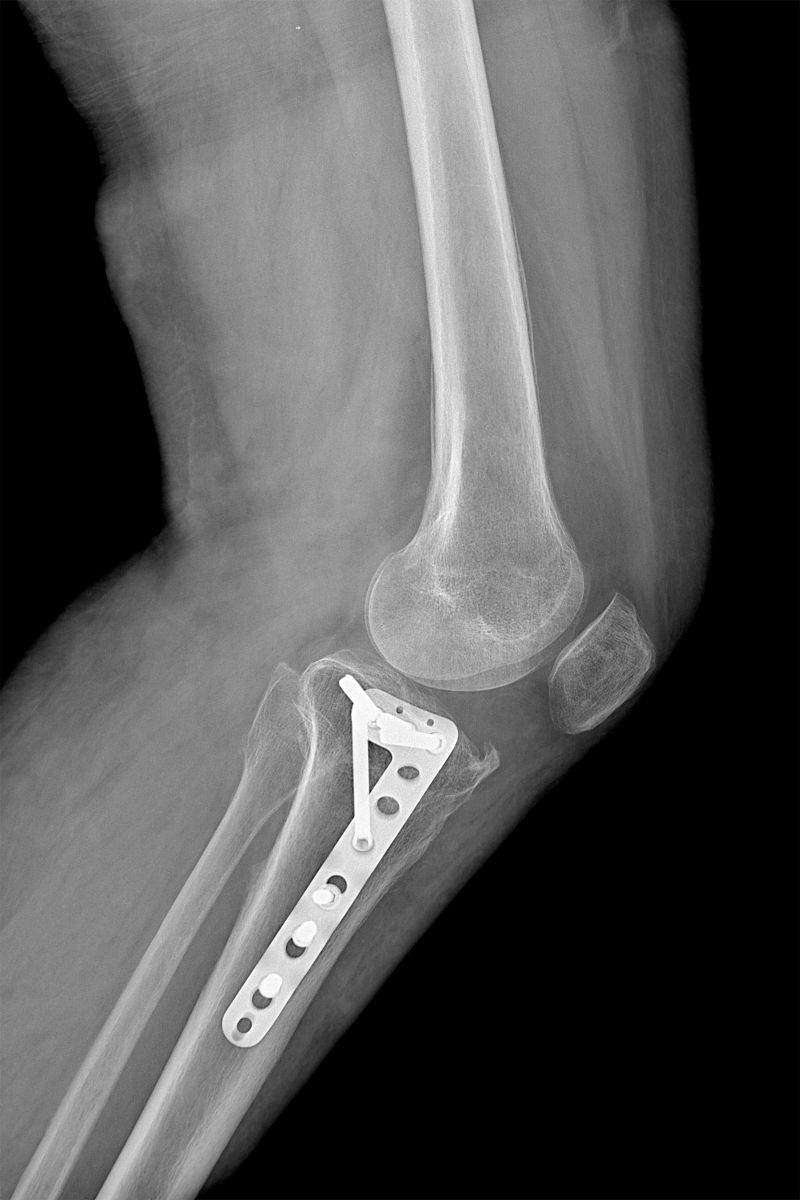

右胫骨平台粉碎性骨折是一种严重的骨折类型,常常需要进行切开复位内固定术来治疗。这种手术的重要性体现在以下几个方面:

总之,右胫骨平台粉碎性骨折患者切开复位内固定术是一种重要的治疗方法,可以恢复关节稳定性,促进骨折愈合,预防并发症,并早期恢复功能。患者应积极接受手术治疗,并在术后进行康复训练,以获得更好的治疗效果。

右胫骨平台粉碎性骨折患者切开复位内固定术治疗的重要性